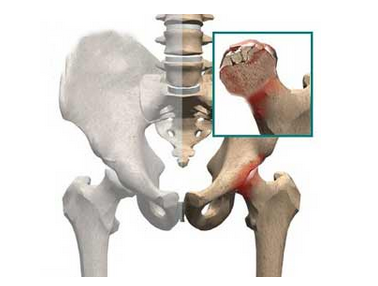

为什么股骨头会出现塌陷的现象

股骨头坏死发生的位置

日饮白酒超半斤 五旬大汉股骨头崩塌